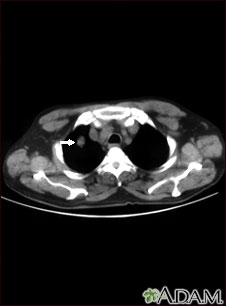

A chest CT may show many disorders of the heart, lungs, mediastinum, or chest area, including:

- A tear in the wall, an abnormal widening or ballooning, or narrowing of the aorta, the major artery carrying blood out of the heart

- Other abnormal changes of the major blood vessels in the lungs or chest such as blood clots (pulmonary embolism)